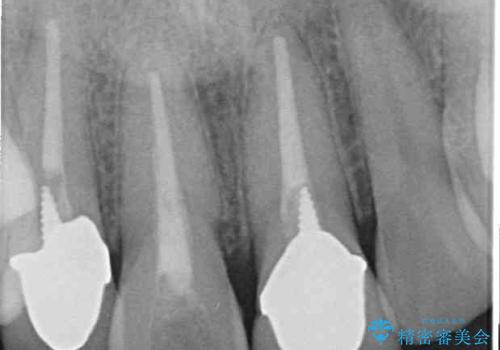

- 前歯の変色した歯を治したいことを主訴として来院された患者様です。

数年前、外傷により両隣の歯とともに根管治療を行い、その後両隣の歯はオールセラミッククラウンにて補綴したそうです。

時間の経過とともに、セラミックにしなかった当該歯の変色が目立つようになり、オールセラミッククラウンにて補綴することとしました。